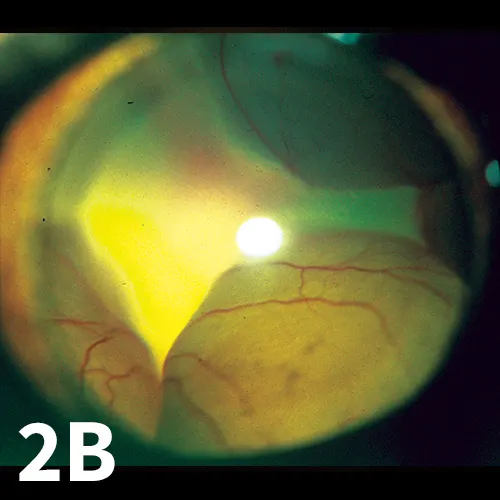

Figure 2

Bullous RD in cats secondary to systemic hypertension. Note the vessels are in different planes of focus. A focal intraretinal hemorrhage is present (A). Images were obtained without use of an ophthalmoscopy lens.

In the normal state, the retina sits directly adjacent to the concave contour of the posterior globe to receive oxygen and nutrients from the choroid, with which it is intimately associated. When the retina detaches, it floats anteriorly within the vitreal chamber and is evident as a thin grey veil with visible vasculature (Figures 1 and 2).